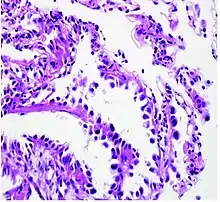

Adenocarcinoma of the lung tends to stain mucin positive as it is derived from the mucus-producing glands of the lungs. Similar to other adenocarcinoma, if this tumor is well differentiated (low grade) it will resemble the normal glandular structure. Poorly differentiated adenocarcinoma will not resemble the normal glands (high grade) and will be detected by seeing that they stain positive for mucin (which the glands produce). Adenocarcinoma can also be distinguished by staining for TTF-1, a cell marker for adenocarcinoma.[18]

As discussed previously, the category of adenocarcinoma includes are range of subtypes, and any one tumor tends to be heterogeneous in composition. Several major subtypes are currently recognized by the World Health Organization (WHO)[1] and the International Association for the Study of Lung Cancer (IASLC) / American Thoracic Society (ATS) / European Respiratory Society (ERS):[19][20][21] lepidic predominant adenocarcinoma, acinar predominant adenocarcinoma, papillary predominant adenocarcinoma, micropapillary predominant adenocarcinoma, solid predominant adenocarcinoma, and solid predominant with mucin production. In as many as 80% of these tumors, components of more than one subtype will be recognized. Surgically resected tumors should be classified by comprehensive histological subtyping, describing patterns of involvement in increments of 5%. The predominant histologic subtype is then used to classify the tumor overall.[2] The predominant subtype is prognostic for survival after complete resection.[22]

To reveal the adenocarcinomatous lineage of the solid variant, demonstration of intracellular mucin production may be performed. Foci of squamous metaplasia and dysplasia may be present in the epithelium proximal to adenocarcinomas, but these are not the precursor lesions for this tumor. Rather, the precursor of peripheral adenocarcinomas has been termed atypical adenomatous hyperplasia (AAH).[10] Microscopically, AAH is a well-demarcated focus of epithelial proliferation, containing cuboidal to low-columnar cells resembling club cells or type II pneumocytes.[10] These demonstrate various degrees of cytologic atypia, including hyperchromasia, pleomorphism, prominent nucleoli.[10] However, the atypia is not to the extent as seen in frank adenocarcinomas.[10] Lesions of AAH are monoclonal, and they share many of the molecular aberrations (like KRAS mutations) that are associated with adenocarcinomas.[10]